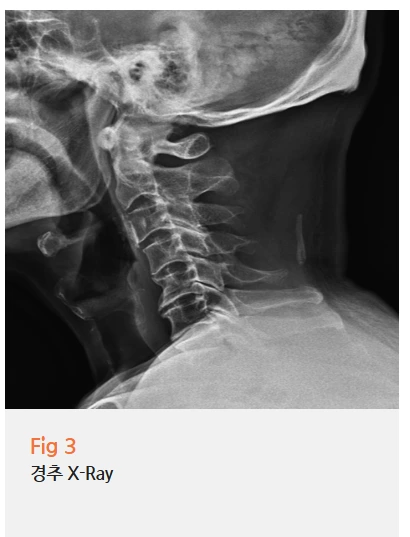

저는 당일 뇌 MRI와 함께 경추 X-ray를 함께 확인했어요.

결과가 꽤 명확하게 나왔습니다.

뇌 MRI에서는 두통을 유발할 만한 특이 병변이 없었어요.

하지만 경추 X-ray에서는 퇴행성 변화가 뚜렷했고,

정상적으로 C자 곡선을 이루어야 하는 경추가

곧게 펴져 있는 변형, 즉 일자목 소견이 관찰되었습니다.